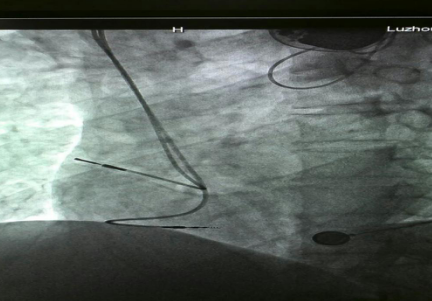

已安裝好的磁共振兼容起搏電極

近年來,隨著醫(yī)學(xué)科技的進步帶動了起搏器的一次次革新,磁共振檢查“大門”已經(jīng)向起搏器患者開放,可以說全面“解禁”磁共振檢查的時代到來了。通過對材料和工藝在內(nèi)的一系列技術(shù)改進,有了可以兼容的磁共振起搏系統(tǒng),包括磁共振兼容脈沖發(fā)生器和磁共振兼容起搏電極。

?“磁共振兼容起搏系統(tǒng)適用于所有起搏器植入術(shù)患者。雖然現(xiàn)在磁共振兼容性起搏器已經(jīng)用于臨床,但是由于整套系統(tǒng)的昂貴價格及醫(yī)保支付等原因,一部分患者因為經(jīng)濟原因暫時不能植入磁共振兼容全套系統(tǒng)?!敝毂蜥t(yī)師表示,心臟起搏器系統(tǒng)包含脈沖發(fā)生器和起搏電極兩部分,起搏電極的拔除和更換手術(shù)較復(fù)雜并且具有一定的風(fēng)險,而單純的脈沖發(fā)生器更換術(shù)則比較簡單。因此,對暫時不能植入磁共振兼容全套系統(tǒng)的患者,可以先植入磁共振兼容起搏電極導(dǎo)線,等到將來各方面條件成熟或需要做磁共振檢查時再直接更換脈沖發(fā)生器。此種方案可以滿足未來患者接受磁共振檢查的潛在需求。